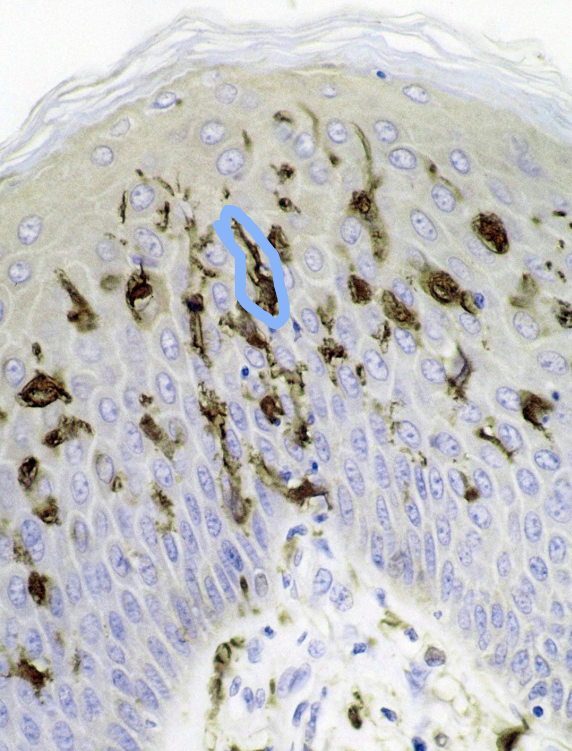

Identify structure that is circled?

Hemidesmosomes that are connecting to the basement membrane (At the dermo-epidermal junction)

Identify the layers indicated by the blue line

Stratum Spinosum

What are key features of the Stratum spinosum?

Keratinocytes

2-10 cells thick

Connected through desmosomes (connects cells to cells)

Identify the blue circles

Desmosomes